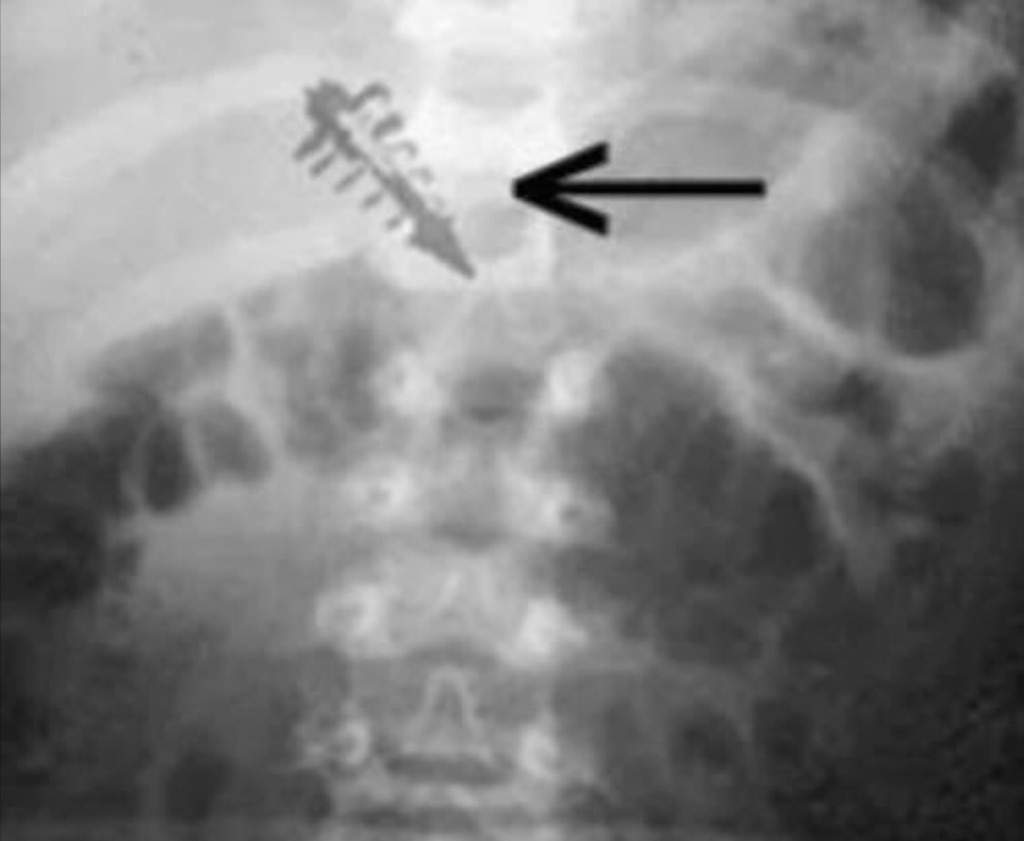

罗杰·莱尔博士可以说是移除外星植入物方面最有“经验”的人。据莱尔博士称,他曾进行过17例手术,取出过来源不明的小型物体。

据莱尔博士称,这些铅笔尖大小的所谓结壳具有磁性,有些甚至会发出无线电频率,这是一种幻觉特征。

其他被检查的物体内部含有陨石碎片;以及镓、锗、铂、钌、铑和铱等金属。

莱尔医生报告说:“这些植入手术的结果非常不寻常。在所有这些病例中,几乎没有出现炎症反应。”

这并非异物组织反应的常见表现。通常情况下,嵌入组织内的异物会导致某种急性或慢性炎症反应,并可能包括纤维化和囊肿形成。但本例并非如此。前两次手术的病理报告显示,金属物体被包裹在一层非常致密、坚韧的灰色膜内,该膜由蛋白质凝块、血红素和纯角蛋白组成。

更直接地说,这些植入物中含有血液蛋白和通常存在于皮肤表层的皮肤细胞。包裹植入物的生物“茧”中也发现了神经本体感受器——与身体该部位组织类型不符的神经细胞和压力细胞。此外,这些植入物茧在紫外光源照射下会发出明亮的绿色荧光。

莱尔博士也曾在互助不明飞行物网络担任顾问医生,他声称,从他身上取出外星物体的人,皮肤上没有可见的疤痕或完整性受损。

虽然没有炎症迹象,但X光片显示有结痂,这几乎是不可能的。